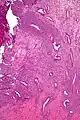

Uterine adenosarcoma have, by definition, a malignant stroma and benign glandular elements. The World Health Organization (WHO) criteria have a mitotic rate cut point; however, this is often disregarded, as bland-appearing tumours with a low mitotic rate are known to metastasize occasionally.[2]

Low mag.

Intermed. mag.

Very high mag.